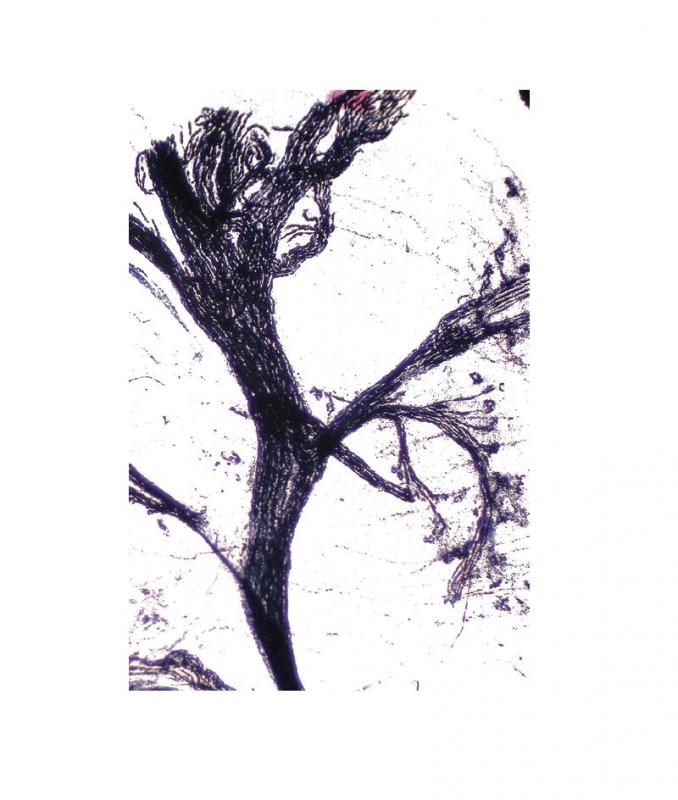

Préparation microscopique: Histologie des vertébrés: Moelle épinière - rat - Cajal CT

Moelle épinière, rat Coupe transversale (CT) Coloration Cajal Préparation microscopique - Biologie animale - Histologie des verterbrés - Système nerveux À l'unité